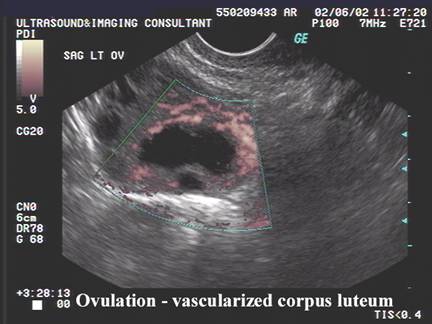

OVULATION

Nakata during the 1992 study, were able to demonstrate that transvaginal ultrasonography, in combination with intraovarian color Doppler flow measurements, is a simple and reliable method to evaluate the size and vascularization of the human CL (3).

Two morphological types of CL were observed following ovulation:

·         with a central fluid-filled cavity (CFFC) (78%),

·         without a central fluid-filled cavity (CFFC).

The incidence of corpora lutea containing a CFFC was greatest immediately following ovulation and then subsequently declined. Prior to this study, the physiological significance of the cystic cavities has not been well-documented. CFFCs were attributed to the chance occurrence of follicle rupture across a vascular component of the follicle resulting in leakage of blood into the follicular lumen. Measurements of the luteal area, defined as the area between the external border of the CL and the internal border of the CFFC, and luteal numerical pixel value (NPV) were the main outcome measures of the study. Luteal area seems highly correlated with progesterone concentrations during the interovulatory interval (IOI). Luteal area and estradiol concentrations, however, were not as strongly correlated. The regressing CL was present in the follicular phase but it did not appear to be functional as indicated by basal levels of serum progesterone and estradiol. This study investigated also the quantitative changes in luteal echotexture that seems reflective of changes in the morphological and physiological status of the CL in women. A decrease in luteal NPV occurred during luteal development in association with an increase in luteal area, progesterone and estradiol concentrations, while the subsequent increase in NPV during luteal regression occurred in association with a decrease in luteal area, progesterone and estradiol concentrations (4). Decreased NPV during luteinization was attributed to increased vascularization of luteal tissue and a corresponding decreased tissue density (4). Increased NPV during luteolysis was attributed to decreased vascularization and replacement of luteal tissue with fibrous connective tissue, reflective of increased tissue density. Unfortunately, in the present study, it was not possible to prove this theory because color Doppler evaluation was not reported (4).